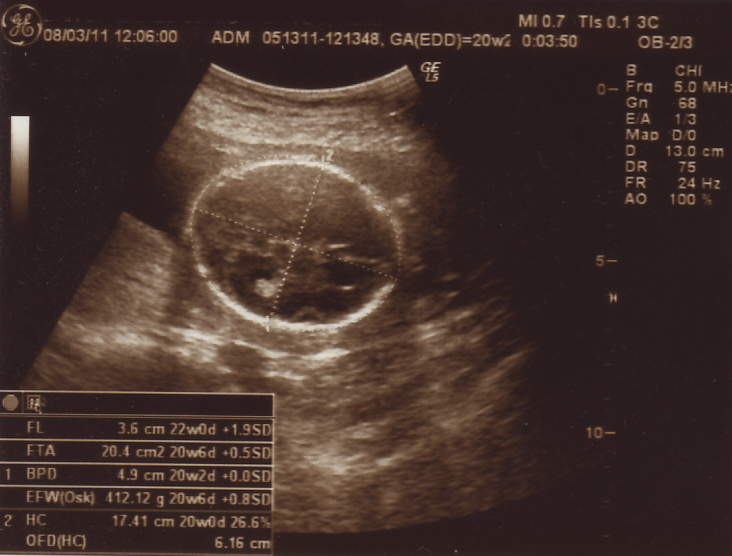

というわけで、今回の検診とエコー画像。

・・・・あたま?( ̄▽ ̄;;)

先生・・・もうちょっと・・・顔だとか手足だとか写ってる写真が欲しいです。。。

えーっと、赤ちゃんの推定の重さって、足の長さと頭の大きさを測って推測するんですねぇ。

これは、頭を測ってるところですよ。

20週相応の大きさのようデス。

ただいま推定412グラム。

4週間前が142グラムだったから、ずいぶん大きくなりましたヨ。